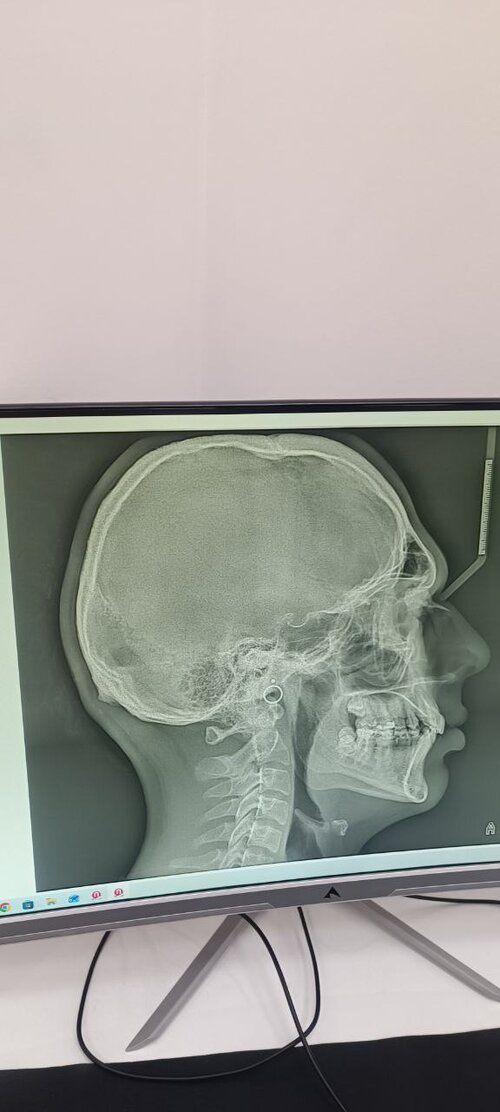

Over for my maxilla?

I can also send front photo